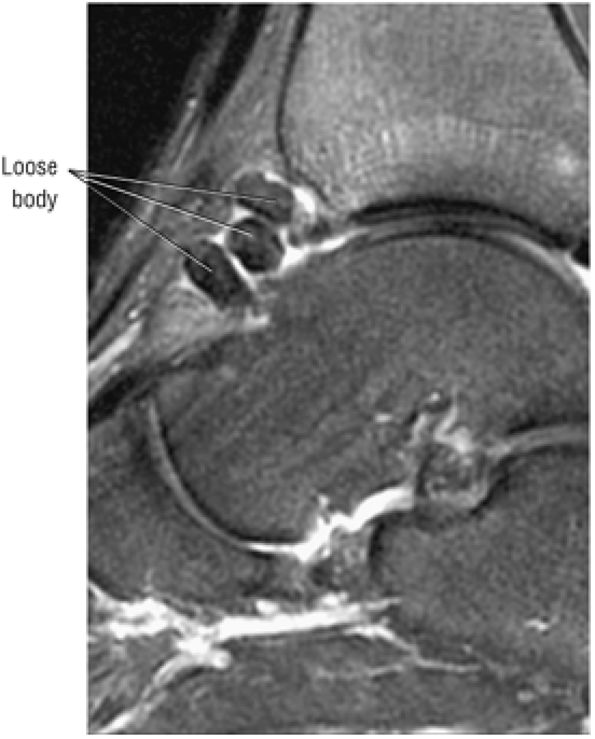

FIGURE 5.98 ● Stage III OLT with fragment adherent to granulation tissue but separated from the overlying chondral surface, (A) Coronal section color graphic. (B) Coronal T1-weighted image. (C) Coronal FS PD FSE image.

FIGURE 5.99 ● Nondisplaced fragment in a stage III OLT with intermediate-signal-intensity granulation tissue at the fragment—talus interface. (A) Sagittal T1-weighted image. (B) Sagittal FS PD FSE image. (C) Color graphic with superior view of talus.